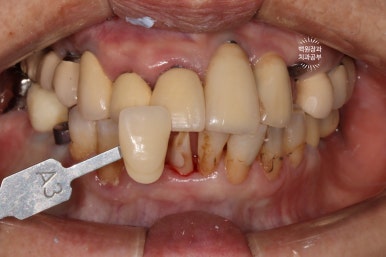

결국 이렇게 지르코니아 크라운 제작이 들어가게 되었고, 색상을 잘 측정하여..

이렇게 예쁘게 완성해드리게 되었죠!!!

저희 치과 지르코니아 크라운은 생각보다 끝내줍니다~! ㅎㅎ